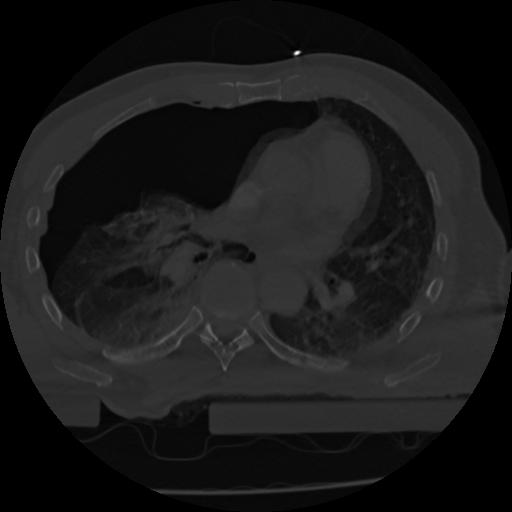

22 ANGIO,CE,Vol,0.5,ANGIO,,